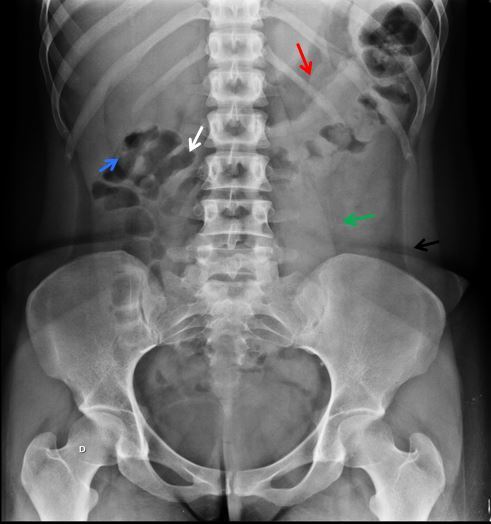

NOME DO EXAME? INCIDÊNCIA? IDENTIFIQUE:

RD SIMPLES DO ABDOME EM DECÚBITO DORSAL.

SETA VERMELHA- ESTÔMAGO

SETA AZUL- CONTORNO DO RIM D

SETA BRANCA – CÓLON TRANSVERSO

SETA VERDE- PSOAS E

SETA NEGRA – FAIXA ADIPOSA LATERAL DO ABDOME ( ESPAÇO PARARRENAL POSTERIOR)

OBSERVE OS PLANOS ADIPOSOS NA CAVIDADE PÉLVICA DELIMITANDO A BEXIGA. ISTO PORQUE TEM TECIDO ADIPOSO CIRCUNDANTE.NUM PACIENTE MAGRO OU EM CRIANÇAS ESTES PLANOS SERIAM INVISÍVEIS.